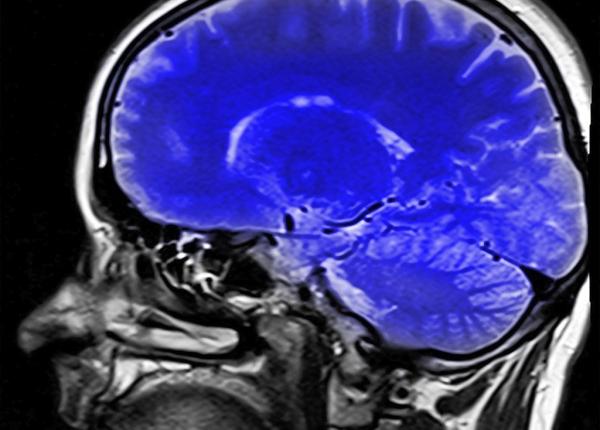

HIV: rolul surprinzător al creierului în răspândirea bolii

Astrocitele, un anumit tip de celule ale creierului, pot ”adăposti” HIV și răspândi virusul în celulele imune.

Cancer pulmonar: de ce se răspândește atât de des în creier

Cercetătorii au aflat explicația răspândirii cancerului pulmonar în creier: o substanță la care nu s-a gândit nimeni.